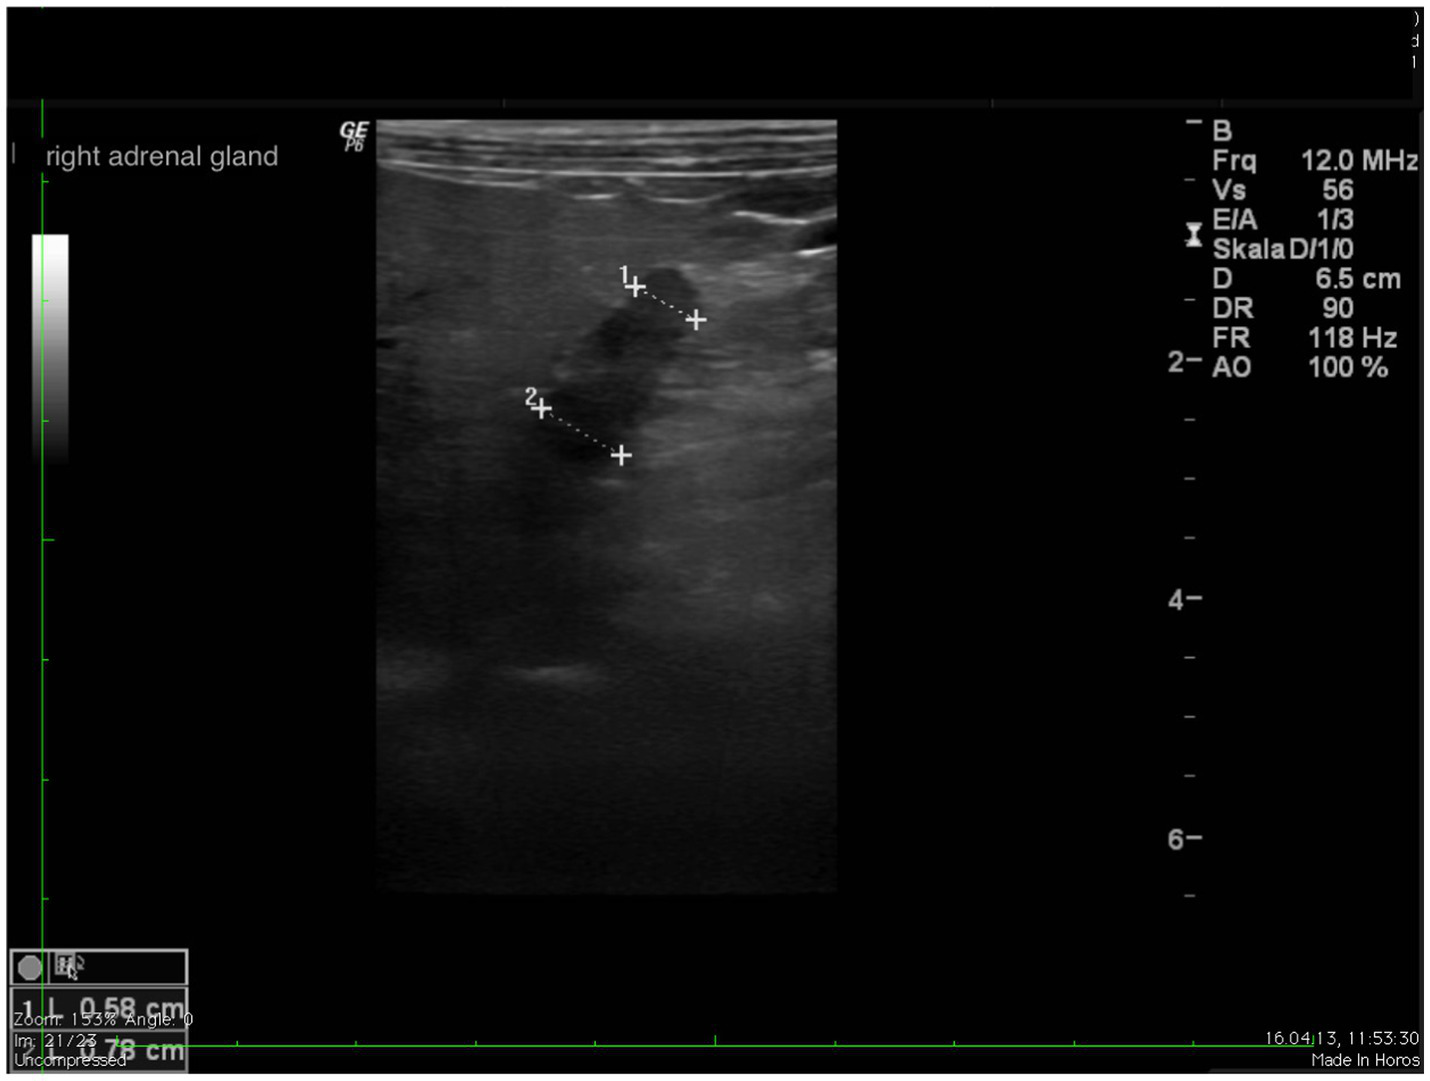

Figure 2

www.frontiersin.org

Figure 2. Ultrasound image of the left adrenal gland with measurement of the cranial and caudal pole (0.54 and 0.5 cm, respectively).

Figure 3

Figure 3. Ultrasound image right adrenal gland with a measurement of the cranial and caudal pole (0.78 and 0.58 cm, respectively).

In all dogs the maximum width of the adrenals was measured. The median maximum width of the left adrenal gland was 0.71 cm (IQR, 0.24 cm) and of the right adrenal gland was 0.75 cm (IQR, 0.19 cm). In a subset of dogs, measurements of the cranial and caudal adrenal poles were available. Thirty-eight measurements of the width of the cranial pole and 41 measurements of the width of the caudal pole of the left adrenal glands, and 38 measurements of the width of the cranial pole and 37 measurements of the caudal pole of the right adrenal glands were available. All detail data are shown in Table 6. The median difference between the two poles of the left adrenal gland (n = 37) was 0.11 cm (IQR, 0.12 cm) and of the right adrenal gland (n = 31) was 0.11 cm (IQR, 0.15 cm; Table 6). Figures 2, 3 show the measurement of a left and right adrenal gland. Figure 4 shows the image of the smallest documented adrenal gland.